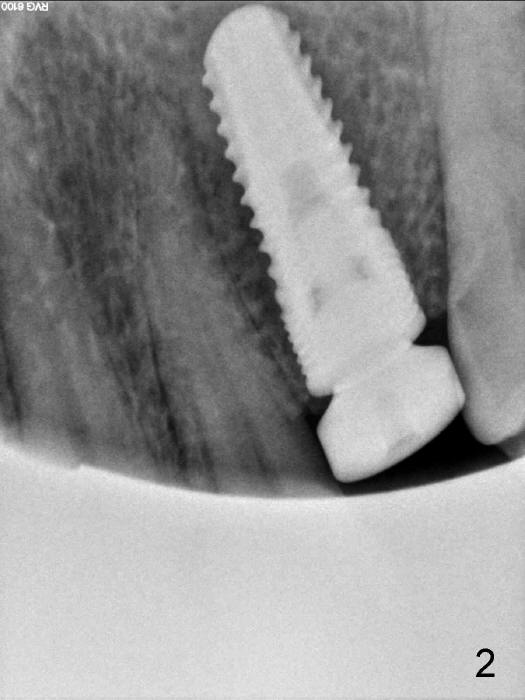

This is today's case; female, 54yrs,coming with broken tooth, I done it 12yrs ago.immediate implant #13 with healing abutment, It took me 40 minuses to dig out the fractured root. The bone spoon You brought to me is very helpful. Thanks!

In fact, a 3.8x8 mm DIO implant is exfoliated. Small implants (3.8 mm in diameter) do not have aggressive threads to achieve primary stability, even though the wrench indicates.  In this case, the healing abutment may contribute to failure.  Additionally, the patient's oral hygiene is not so good.   Do you have any good idea how to fix this case?  Thanks.